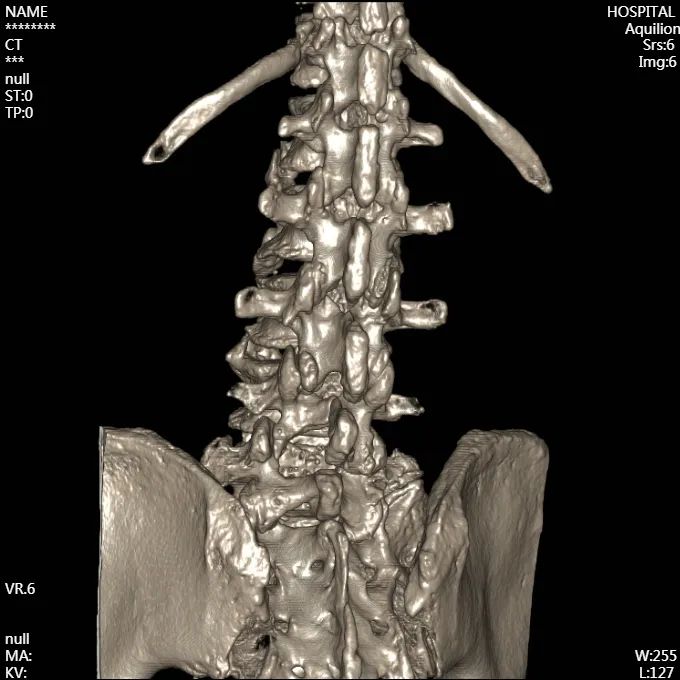

腰椎CT成像

從影像上看出,患者術(shù)后神經(jīng)壓迫情況得到了改善